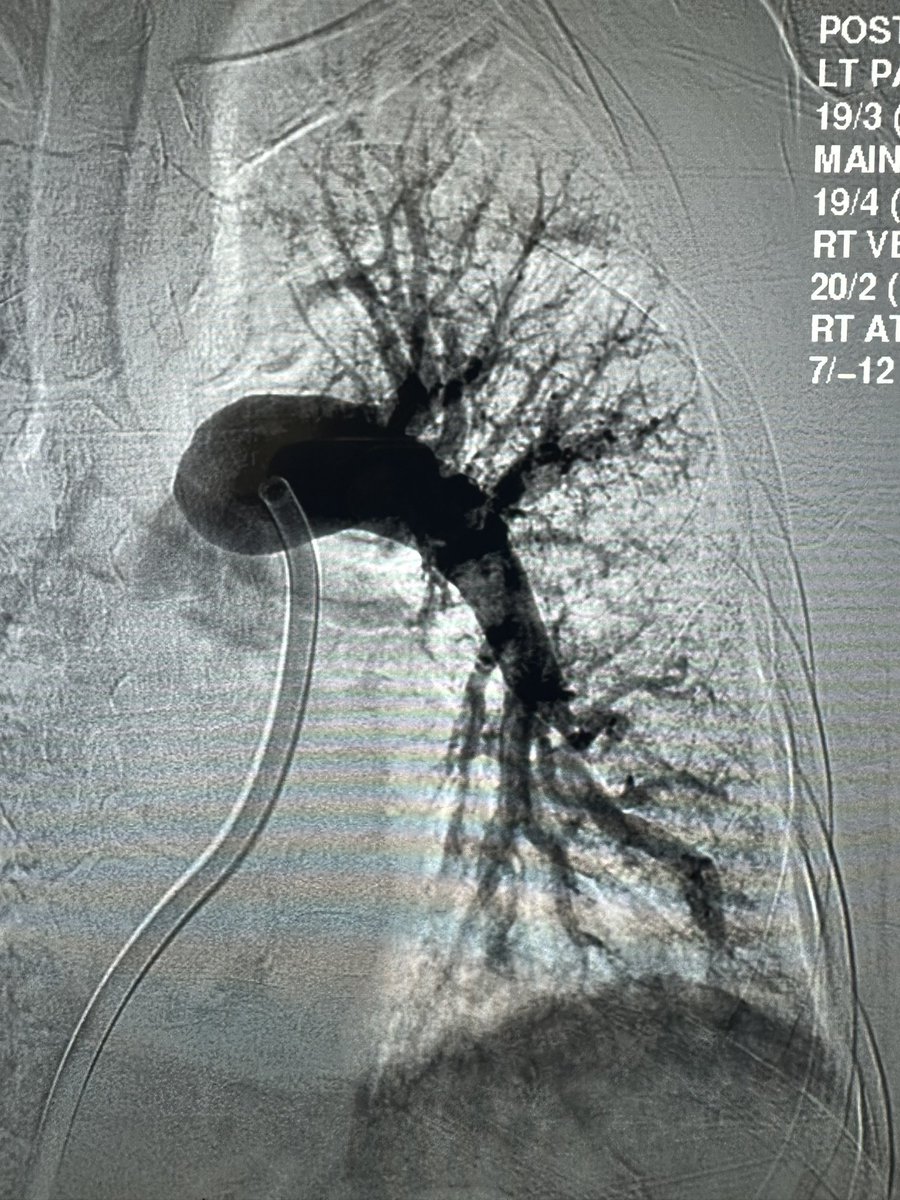

Two patients with repeat CT (chest pain episode) within 3 weeks after PE thrombectomy Penumbra (Flash 16). Patient1 submassive extensive bilateral PE on presentation ->complete resolution, Patient2 saddle embolus repeat CT—> tiny remnant thrombus both with resolution of RV strain

PE with new FLASH 2.0 for the win! From Non-rebreather —>97% on room air, PA pressure drop 44–>19mm & Flouro time 11 mins. At my age I like PE cases under 40 minutes ! #speedyPE #CAVT @roblookstein @keithppereira @t_intheleadcoat @vaheesanIR @SIRspecialists

US HCPs: Congrats to Dr. Robert Sanchez at @uthealtheasttx on this bilateral PE! ⚡ Lightning Flash 2.0, next-gen software for the treatment of PE. #CAVT #GallopMode Rx only. Risk info: peninc.info/risk Clinical results may vary